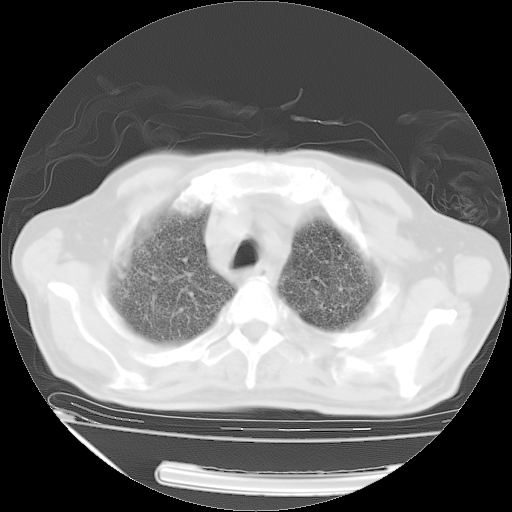

甲强龙80mg/日+抗结核治疗(异烟肼+利福霉素+乙胺丁醇)10天。复查肺部CT。

治疗10天肺部CT

仔细阅读病史资料和CT,我觉得两肺粟粒结核要高度怀疑。